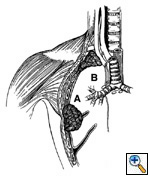

Fig.

10: T3: A tumor

of any size with direct

extension into the (a)

chest wall, including (b)

superior sulcus tumors,

or the diaphragm, mediastinal

pleura or pericardium,

without involving the heart,

great vessels, trachea,

esophagus or vertebral

body, or a tumor in the

main bronchus within 2

cm of the carina without

involving the carina. |

Limited, circumscribed, extrapulmonary extension

of the primary tumor is designated T3.